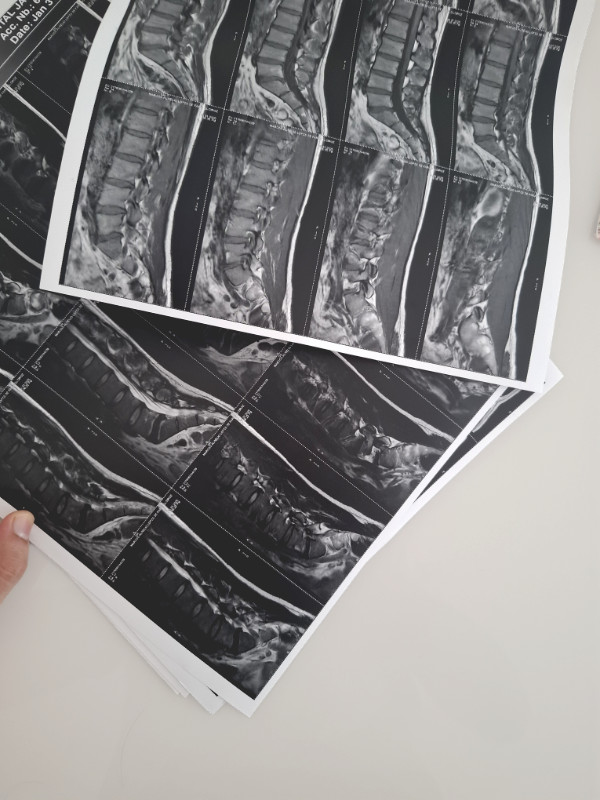

Então, agendei minha consulta no ortopedista que me pediu alguns exames e lá vai minha esposa agendar horário para mim novamente. Fui lá no Centro de Imagens do hospital. Acredita que em pleno verãozão jaraguaense, quando estava fazendo a ressonância eu até tirei uma sonequinha? Não pode deixar de aproveitar o friozinho não né. Depois fui lá e fiz a radiografia da coluna.

No exame mostrou que existem alguns desgastes, algumas compressões e falta de líquido em alguns discos. OK. Na minha ignorância, eu pensei que o melhor seria perder peso, melhorar a parte muscular e a postura, dieta e ingestão de água, mas agendamos a consulta na fisioterapeuta que me disse que era mais ou menos isso mesmo e que tinha que fazer pilates também. Já era o que esperava ouvir mesmo. Às vezes a gente só faz o exame para confirmar as nossas suspeitas.